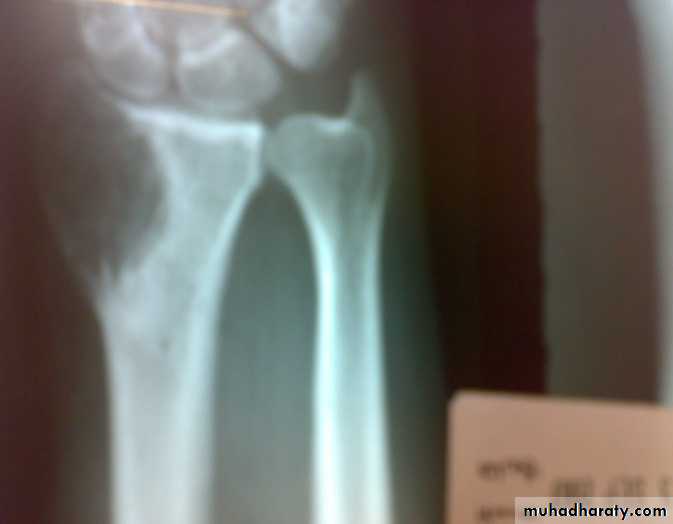

Patient presented by local pain and swelling or pathological fractures. Common site is the distal femur, proximal tibia, distal radius.

X-ray show eccentric osteolytic lesion in the end of long bone ,subchondral, trabeculated (soap bubble appearance). The cortex is thin, expanded or even perforated.